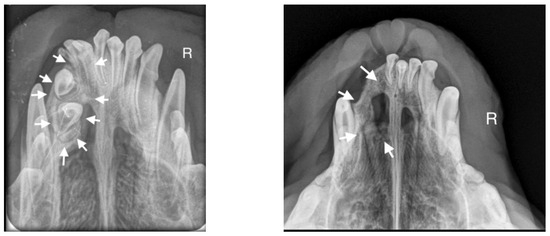

A 10-month-old American Staffordshire Terrier dog was referred for an orthodontic consultation due to abnormal alignment of the maxillary teeth and the resulting bite injuries. Clinical examination revealed three properly aligned incisors on the right side and four incisors (including one tooth with a double crown) on the left side arranged chaotically (Figure 7). Intraoral examination revealed an abnormal palatal crease in the projection of teeth 103–203 and a hard and painful protrusion about 3 cm in diameter on the left side. The roentgenogram showed the presence of three additional incisors, including two unerupted ones, growing in the opposite direction to the alveolar process. The double tooth on the X-ray appeared to be a fused tooth (tooth fusion occurs as a result of physical force or pressure on an adjacent tooth’s bud, leading to the contact of the two tooth buds and their fusion before calcification) [12]. The abnormal growth of the incisors on the left side caused pressure on the incisal bone, along with skewing of the nasal septum to the right side (Figure 8). The third incisor, along with an additional third incisor, showed radiographic features of a dentigerous cyst. A decision was made to perform open extraction of the ectopic teeth using the CLP method.

The bone cavity, after such a large open extraction, was 3.0 cm × 4.2 cm; so, the decision was made to implant polymeric hydroxyapatite with curdlan soaked in 0.9% NaCl into the areas of bone loss. The flap was sutured with 4-0 monofilament single sutures. A follow-up radiograph was taken 28 days after surgery. On clinical examination, the soft tissues were healed properly. On the follow-up radiograph, the bone tissue was healed properly, with new bone formation.

Figure 8. Intraoral photograph of the dog. On the left side of the dog’s mouth, chaotic tooth growth (marked with arrows) and atypical curvature within the palatal crease with displacement to the left side of the incisor papilla are visible.